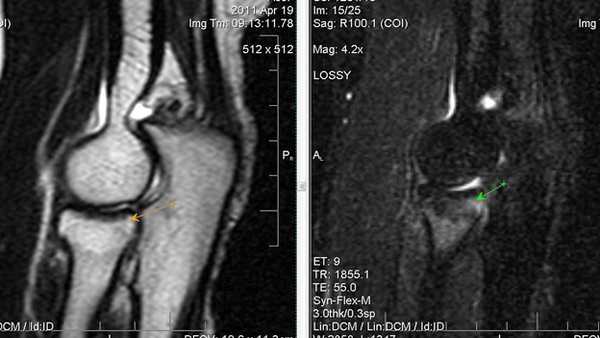

МРТ картина синовита, стрелками указаны участки отека костной ткани локтевого отростка

Синдром поражения суставов

Большинство изменений локтевого сустава сопровождается симптомами сопутствующего экссудативного синовита; его выраженность зависит от тяжести травм. На МРТ выявляется суставной выпот. Кроме того, иногда определяется отек костного мозга в субхондральных отделах эпифизов костей, отек периартикулярных мягких тканей.

Ревматоидный артрит III стадия выпот в полости сустава (1), грубое эрозирование субхондрального слоя головки плечевой кости (2), фрагментация суставной губы гленоида.

Ревматоидный артрит, II ст. субхондральные жидкостные кисты в эпифизе плечевой кости (1), краевые узуры лучевой кости.

Ревматоидный артрит, III ст. субхондральные эрозии (1) и краевые узуры (2) дистального эпифиза плечевой кости, наличие суставного выпота (3) и массивная гипертрофия синовиальной оболочки (4).

МР признаки артроза локтевого сустава l ст. Синовит.

МР признаки более специфичны для латерального эпикондилита; деформирующего артроза ll ст. локтевого сустава. Синовит.